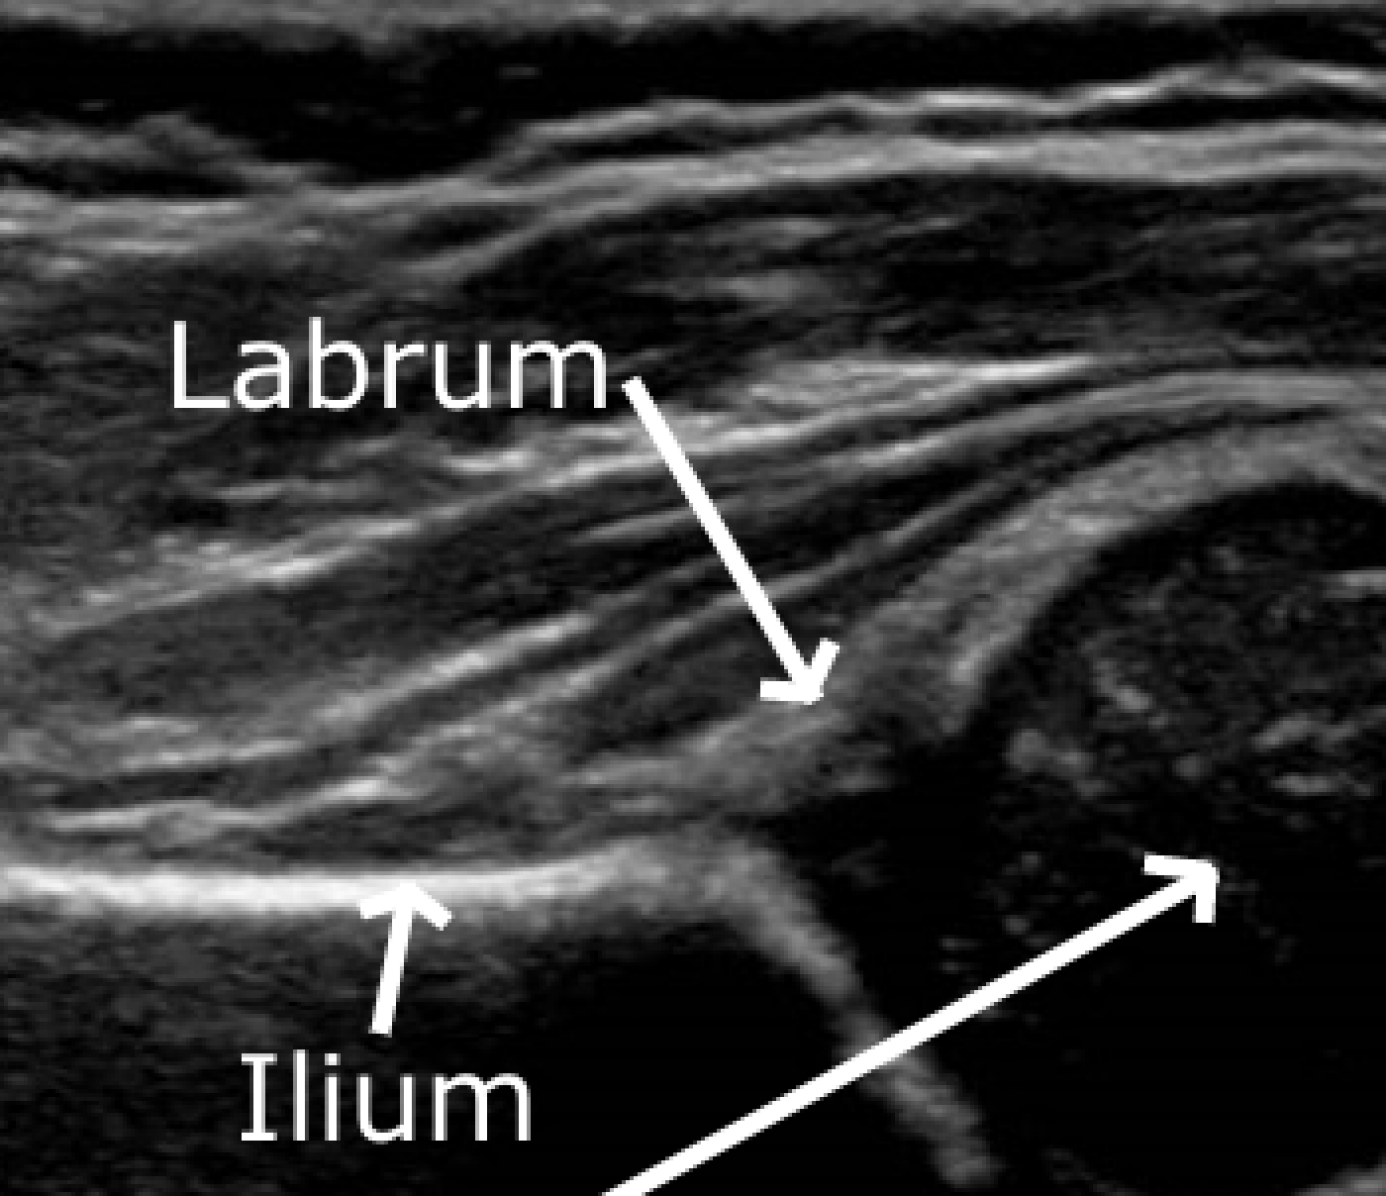

Ultrasound imaging is more sensitive (clinically) than a physical examination and is ideal for screening programmes as it is safe and portable [3]. The Femoral Head Coverage (FHC) method is used to provide objective evidence where a straight line is drawn extending along the upper edge of the ilium (Fig. 1) and the femoral head proportion on each side of the line is measured [4]. Clinically, a decision value of 50%percent5050\% coverage is used, with a larger percentage below the line (FHC>>50%) identified as healthy and a larger percentage above the line (FHC\leq50%) termed DDH [5].

State of the art literature for automatic DDH evaluation uses the Graf method [6, 7, 8]. However, this method has extremely high inter-operator variability and it only achieves approximately 85% agreement with clinicians. Our reproducible algorithm takes automated numerical measures of the FHC (AFHC) to classify the presence or absence of DDH. It does so by segmenting key anatomical structures from static 2D ultrasound images: ilium, femoral head and labrum (Fig. 1). Clinicians are able to identify these structures and diagnose by simply inspecting the scan (Gestalt laws) [9].

Fig. 1: (a) Static ultrasound of hip joint, annotated with femoral head, ilium and labrum. (b) Measurements required for FHC evaluation: FHC%=AB×100percentFHC𝐴𝐵100{\textsc{FHC}}\%=\frac{A}{B}{\times}100.